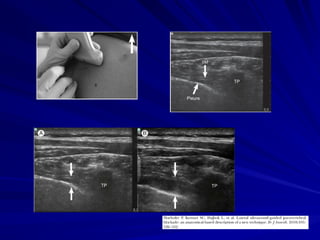

Bloqueos ecoguiados

La incorporación del ultrasonido (US) a la

anestesia regional, ha permitido que cada

vez con mayor frecuencia se realicen

bloqueos ecoguiados.

Destacan varios trabajos realizando BPVT

bajo US, con técnicas variadas,

describiéndose abordajes sagitales

transversales y oblicuos, con visualización

de la aguja en plano y fuera de plano.